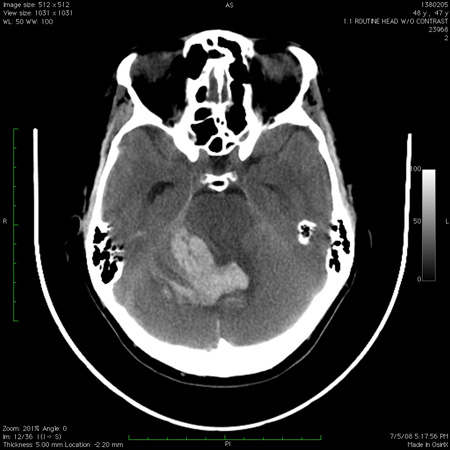

Work-up with imaging of the brain (CT scan, MRI with diffusion-weighted imaging sequence) is required to look for signal changes associated with stroke, demyelination, or cerebellitis.[128][132][133][134] CT imaging in children necessitates the use of dedicated paediatric protocols to minimise radiation exposure.[134][Figure caption and citation for the preceding image starts]: Acute bilateral cerebellar infarct, as seen on diffusion-weighted imaging sequence magnetic resonance imageFrom the collection of Dr S. H. Subramony; used with permission [Citation ends].

[Figure caption and citation for the preceding image starts]: Computed tomography scan of the brain showing a haemorrhage in the cerebellum with extension into the fourth ventricleFrom the collection of Dr S. H. Subramony; used with permission [Citation ends].